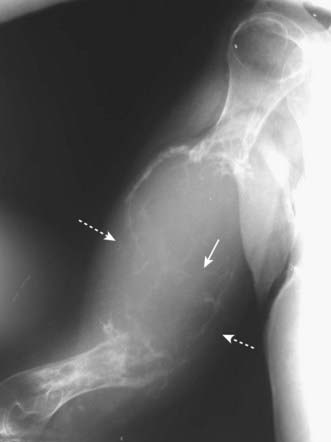

image On conventional radiographs, the region of avascular necrosis appears denser than the surrounding bone. On MRI, there is usually a decrease from the normal high signal produced by fatty marrow (Fig. 21-8).

image The devascularized bone becomes denser and therefore appears more sclerotic than the remainder of the bone. This especially occurs in the femoral head (Fig. 21-9) and humeral head (Fig. 21-10).

image

Figure 21-8 Avascular necrosis, MRI.

A T1-weighted coronal view of both hips demonstrates normal high signal from the fatty marrow in the right femur (dotted white arrow) but decreased signal in the left femoral head extending to the subchondral bone of the left hip joint (solid white arrow). The joint space is preserved.

Figure 21-10 Avascular necrosis of humeral head.

There is increased density seen at the very top of the humeral head (solid black arrow) in this patient with sickle cell disease who developed avascular necrosis of the humeral head. Because the white cap on the bone looks like snow on a mountaintop, this sign of avascular necrosis has been called snow-capping.